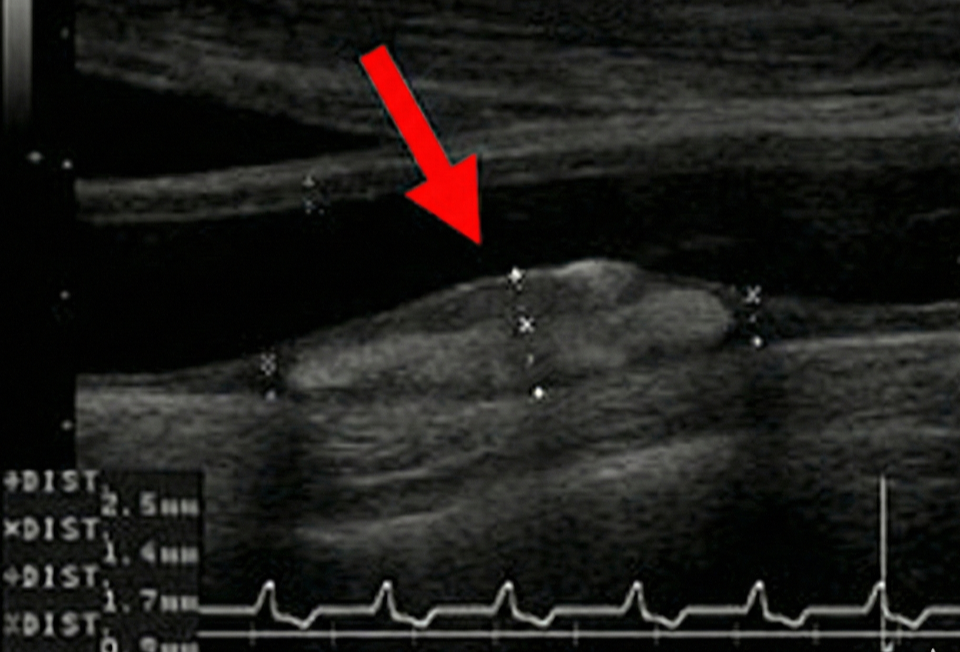

脂質異常症(頸動脈エコー像)

2.「白黒つける」ための即日精密検査(頸動脈エコー)

当院では、首の血管を超音波で診る「頸動脈(けいどうみゃく)エコー」を行い、「実際にあなたの血管が詰まり始めているか」を目で見て確認します。

判定B【プラーク(コブ)がある場合】

残念ながら、動脈硬化がすでに始まっています。

この場合、コレステロールの数値がそこまで高くなくても「治療開始の明確なサイン」となります。

将来の脳梗塞や心筋梗塞を確実に防ぐために、お薬の力を借りましょう。